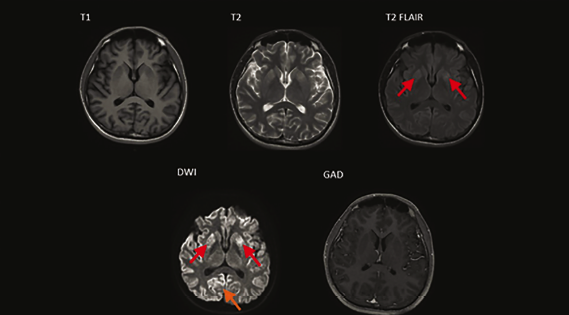

La sintomatología progresó con episodios depresivos y labilidad emocional con tendencia a la irritabilidad, 3 semanas después se agregó desorientación, disminución de fuerza en hemicuerpo izquierdo y latero pulsión de la marcha ipsilateral. Fue ingresado a hospitalización donde se realizaron distintas pruebas entre las cuales destacaron como positivas la proteína 14-3-3, proteína TAU 15,134 pg/ml (normal 0-1150 pg/ml), y resonancia magnética, la cual presentó “listón cortical”, e hiperintensidades en los núcleos de la base (figura 1), a su vez cabe destacar que no hubo mutaciones para el gen PRNP, pero presentó una mutación silenciosa en el codón 117 y polimorfismo en Val en codón 129.

Imágenes: Guevaraet al.

Figura 1. En las imágenes de resonancia magnética en cortes axiales donde se observan cambios en los núcleos de la base en las secuencias potenciadas en T2 donde se observa restricción simétrica en la cabeza del núcleo caudado (flecha roja) y restricción a la difusión en DWI asimétrico cortical, signo del listón cortical (flecha naranja).

La resonancia magnética es otra herramienta importante en el diagnóstico diferencial de una demencia rápidamente progresiva y tiene una alta sensibilidad y especificidad en el diagnóstico de ECJ, nuestro paciente presentó hiperintensidades en los núcleos de la base y encorvamiento cortical, hallazgos incluidos en los criterios de resonancia magnética para ECJ de la universidad de San Francisco 2010. Para integrar estos criterios usamos el consenso de la universidad para la probabilidad de la enfermedad, siempre descartando otras patologías siguiendo el algoritmo VITAMINS propuesto por Geschwind2,16.